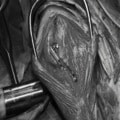

関節穿刺を行い、好中球はなく、少数のマクロファージや滑膜細胞が認められるました。膝蓋骨脱臼および前十字靭帯断裂による退行性の関節炎を疑い、関節鏡検査を実施いたしました。関節鏡検査では、重度の滑膜炎および前十字靭帯の完全断裂が認められました。内外側とも半月板に損傷は認められませんでした。

■ 外科的治療法

断裂前十字靭帯の除去を行いました。外側方向からのテンションが著しく、外側広筋と膝関節外側支帯の解放を行いました。膝関節伸展機構の著しいアライメント異常が認められたため、脛骨粗面転移術を実施しました。

写真の膝関節の垂直線を綿棒の木柄が表しており、遠位の脛骨粗面との位置関係が平行ではありません。